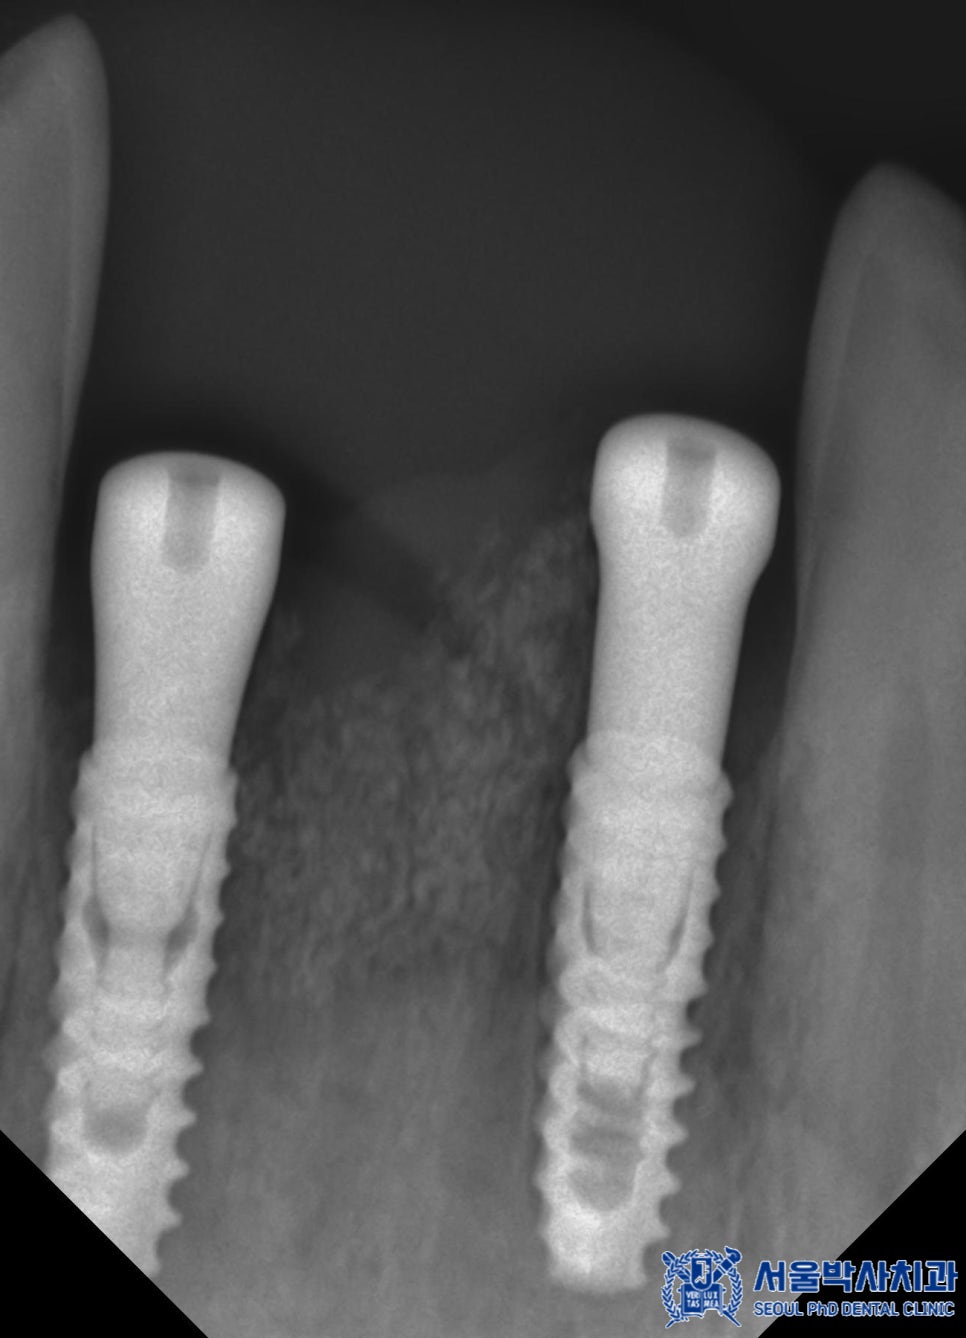

특히 아래쪽 앞니 부위는 오랜 기간 치아가

빠져 있던 탓에 뼈가 많이 흡수된 상태였습니다.

이때 임플란트를 안정적으로 고정하기 위해서는

충분한 골량이 필요하기 때문에

해당 부위에는 뼈이식을 함께 진행하기로 했습니다.

약 2개월 후, 임플란트가 안정적으로

자리 잡은 것을 확인한 뒤

최종 보철물을 제작하였습니다.